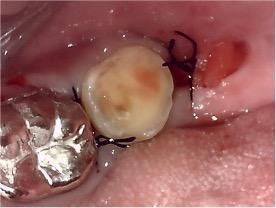

上の写真はなんと親知らずが、手前に移動しています。

下の一番奥歯がなくなって、親知らずを手前に移植しました。